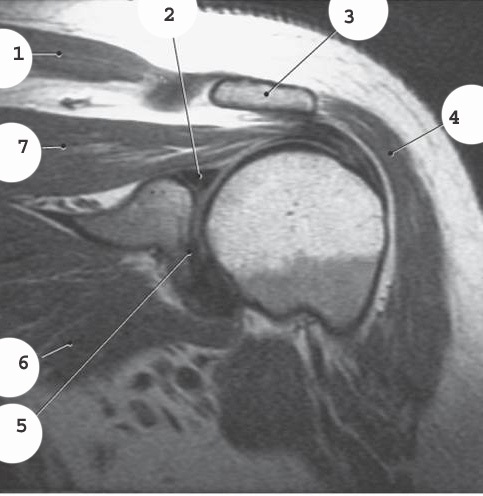

1

labrum

3

infraspinatus muscle

4

deltoid

2

acromion